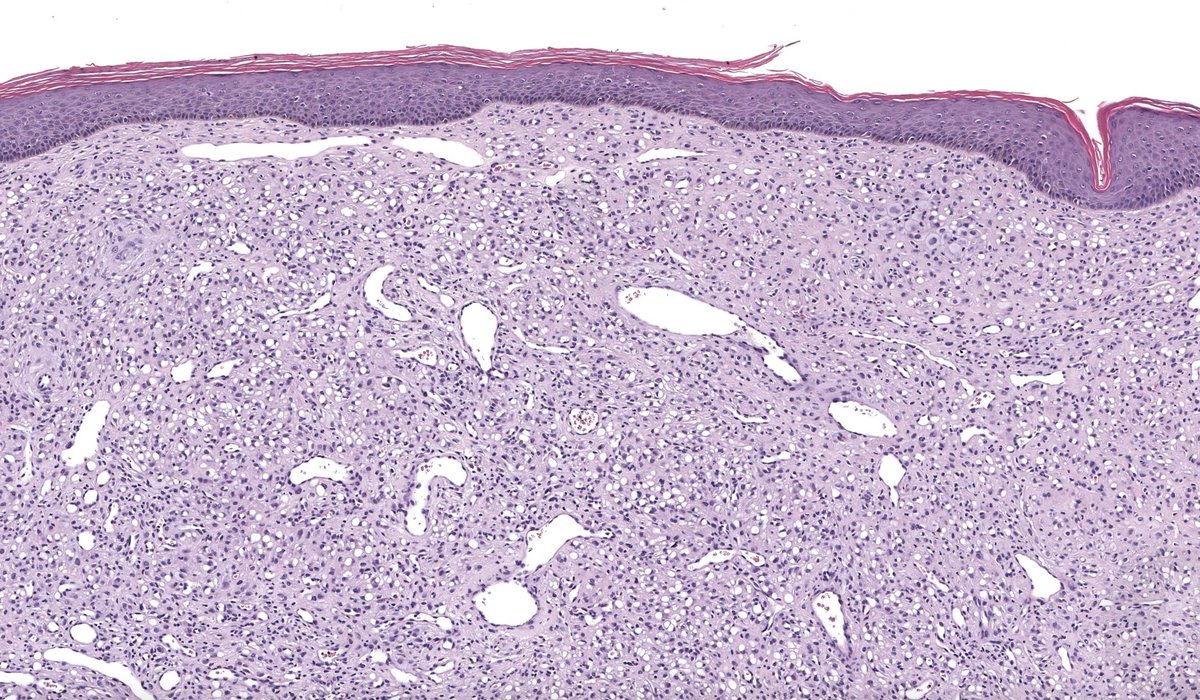

Pathologists! What do you make of this enlarged pre-articular lymph node in adult male originally from India? Otherwise, asymptomatic, no enlarged nodes away from head and neck. #HemePath #Lymphadenopathy #lymphnode